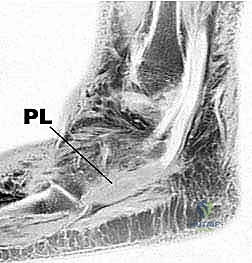

تتكون مجموعة أوتار الشظية من وترين رئيسيين ينشآن من عضلات في الجزء الجانبي (الخارجي) من الساق، وينزلان معًا خلف عظمة الكعب الخارجي:

- الوتر الشظوي القصير (Peroneus Brevis):

ينشأ هذا الوتر من العضلة التي تغطي الثلثين السفليين من عظم الشظية الجانبي في الساق. يتجه وتره إلى الأسفل والأمام، ليكون أعمق (أقرب للعظم) بالنسبة لوتر الشظية الطويل أثناء مرورهما خلف الكعب الجانبي (Lateral Malleolus). ينتهي هذا الوتر بالالتصاق بقوة في قاعدة مشط القدم الخامس (العظمة البارزة في منتصف الحافة الخارجية للقدم).

وظيفتة الأساسية: هي قلب الكاحل للخارج (Eversion)، مما يمنع القدم من الالتواء للداخل، بالإضافة إلى المساعدة في ثني الكاحل ظهريًا (Dorsiflexion). نظرًا لموقعه التشريحي المحصور، فهو الأكثر عرضة للتمزق الطولي الاحتكاكي. - الوتر الشظوي الطويل (Peroneus Longus):

ينشأ من منطقة أعلى في الساق، تحديدًا من رأس الشظية والثلثين العلويين من عظم الشظية الجانبي. يتجه وتره إلى الأسفل ليكون سطحيًا (فوق أو خلف) وتر الشظية القصير عند الكعب الجانبي. بعد تجاوزه الكعب، يغوص هذا الوتر تحت باطن القدم (الجانب الأخمصي)، ليعبر القدم قطريًا ويدخل في قاعدة مشط القدم الأول والعظم الإسفيني الأول في الجهة الداخلية للقدم.

وظيفته الأساسية: إنه قالب قوي للخارج (Evertor) ومثني أخمصي (Plantarflexor) لمشط القدم الأول. كما أنه يساهم بشكل حاسم في الحفاظ على القوس الطولي والعرضي للقدم أثناء مرحلة الدفع في المشي.

- الرباط الشبكي الشظوي العلوي (Superior Peroneal Retinaculum - SPR):

هو الهيكل الأهم لمنع خلع الأوتار. عبارة عن شريط ليفي قوي يتراوح طوله بين 1 إلى 2 سم، ويمتد من الحافة الخلفية الجانبية لعظم الشظية إلى الجدار الجانبي لعظم الكعب (Calcaneus). دوره الأساسي هو إبقاء أوتار الشظية داخل التلم (التجويف) المخصص لها خلف الكعب الجانبي. إذا تعرض هذا الرباط للتمزق أو الارتخاء (غالبًا بسبب التواء شديد للكاحل)، فإن الأوتار تبدأ بالانزلاق أو الخلع (Subluxation) من مكانها بفرقعة مسموعة، مما يؤدي إلى تمزقات احتكاكية لاحقة. - الرباط الشبكي الشظوي السفلي (Inferior Peroneal Retinaculum - IPR):